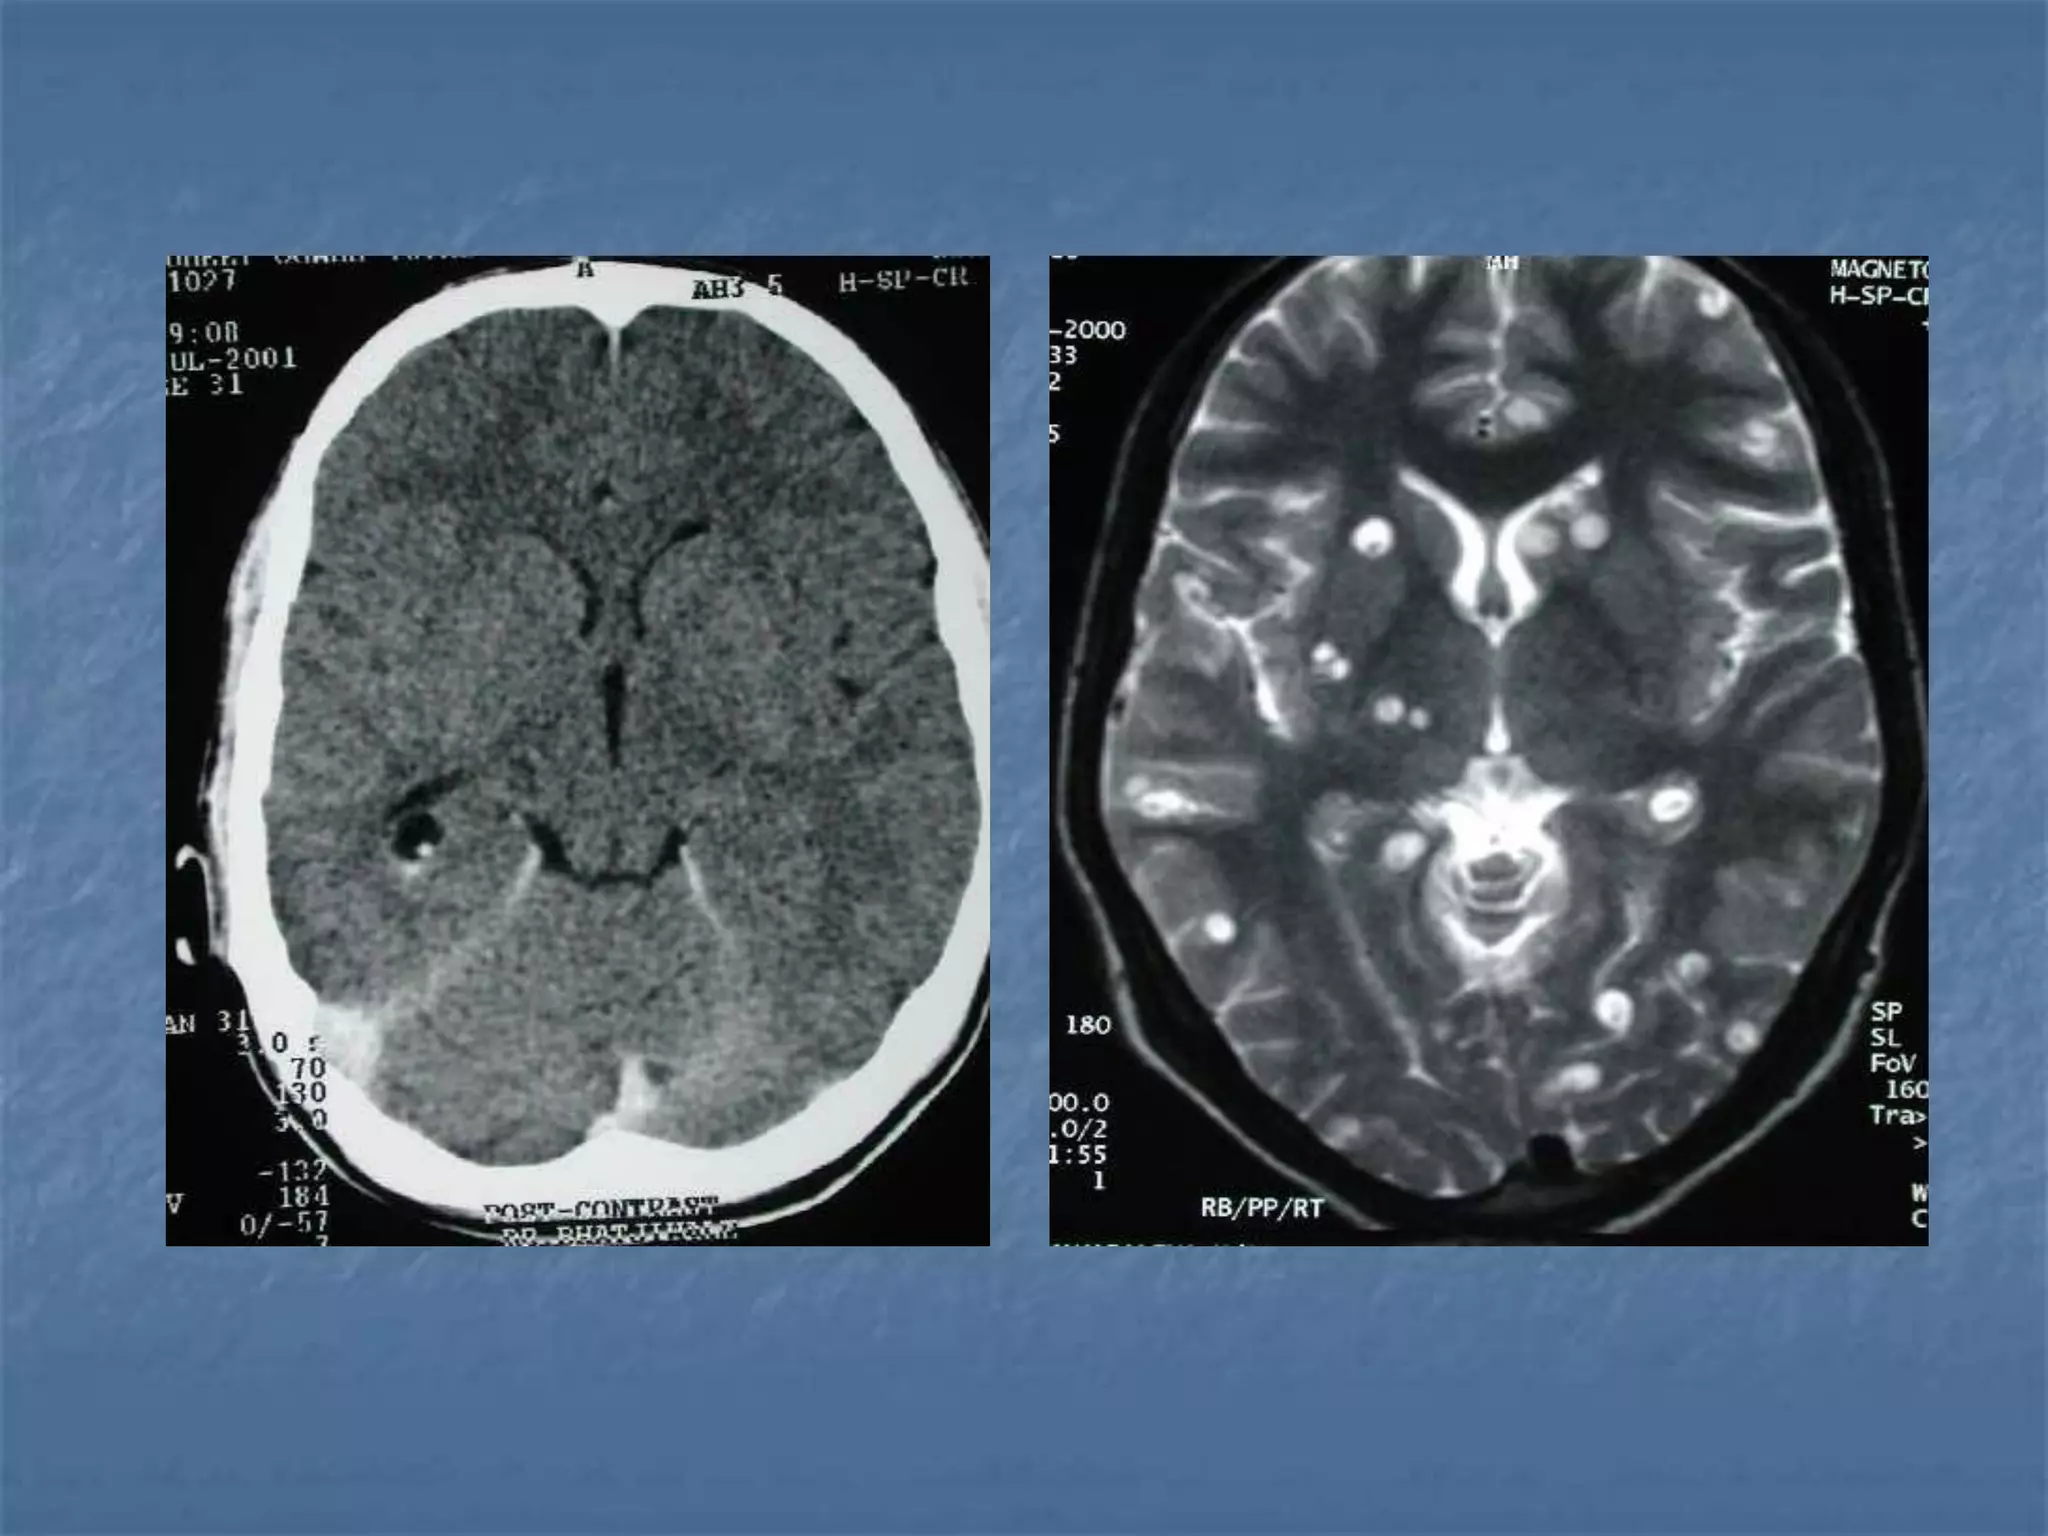

ARTERIOVENOUS MALFORMATION

Stroke in Children Constitutes 3% of cerebral infarcts

 Most common cause is congenital heart

disease. Other causes are vasospasm &

vasculitis,

 Echo, CT, MRI & catheter angiogram

should be performed as and when

required.